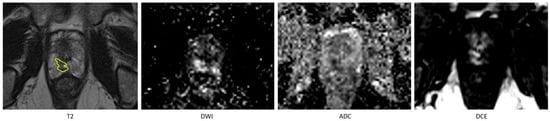

3.1. Tumor Detection

In the comparison between the radiologist and the fully automated AI method, a total of 175 lesions were manually annotated across the 120 included patients. The fully automated AI method achieved a recall of 0.74 and a precision of 0.76 in detecting these lesions. When comparing the radiologist’s segmentations to those of the AI-assisted model, the AI-assisted method demonstrated substantial improved performance, achieving a recall of 0.95 and a precision of 0.94. Detailed metrics are provided in Table 1. An example of missed lesion (false negative) by the fully automated AI method is demonstrated in Figure 2.

Figure 2. An example of missed lesion (false negative) by the fully automated AI method, where lesion is annotated by the radiologist (in yellow) on T2 hypointense area in the peripheral zone in the right apex with corresponding high signal on the high-B-value DWI and low signal on the ADC and on the DCE early enhancement.